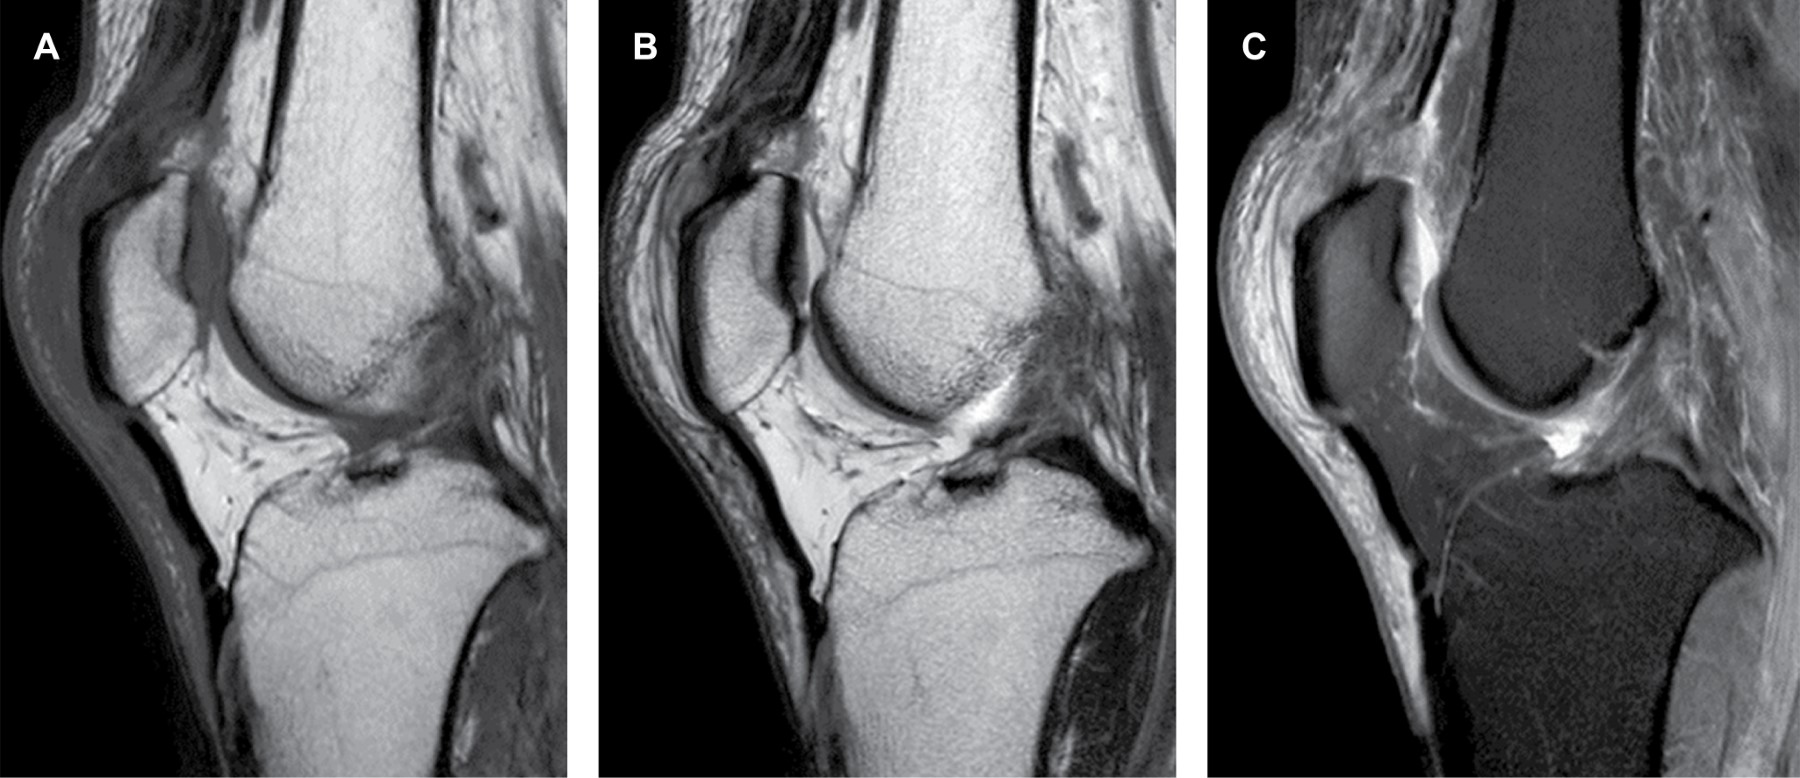

Masculino de 45 años sufre traumatismo directo en tercio distal de la cara anterior del muslo izquierdo, valorado por médico ortopedista quien observó aumento de volumen acompañado de edema prepatelar, doloroso a la palpación, depresión a la palpación en la topografía del tendón del cuádriceps, dolor a la flexión pasiva y activa. El ultrasonido muestra pérdida del patrón fibrilar e interrupción de la mayor parte de las fibras del tendón del cuádriceps (Figura 1); en forma complementaria se decide solicitar estudio de resonancia magnética de rodilla donde existe ruptura completa del tendón del cuádriceps en su inserción y como signo indirecto, situación de rótula baja (Figuras 2 A-C). Las lesiones del cuádriceps tienden a ser comunes entre atletas y adultos activos, desde contusiones musculares leves hasta la ruptura completa del tendón. El cuádriceps se compone del recto femoral, vasto lateral, vasto medial y vasto intermedio; éstos se insertan en la rótula como el tendón del cuádriceps común. El tendón envuelve la rótula y se inserta en la tuberosidad tibial.1 La localización de la ruptura se demuestra que está a 1-2 cm de la parte superior del polo rotuliano , en la mayoría de los casos en la región avascular del tendón.2 La edad de presentación ocurre en adultos mayores de 50 años o atletas más jóvenes.3,4 El paciente puede experimentar sensación de desgarro en la rótula o "explosión" seguida de aumento de volumen y dificultad para soportar el peso.5 Es posible desarrollar hemartrosis aguda y sensibilidad focal por encima de la rótula, no se puede mantener la pierna recta ni levantar la pierna contra la gravedad mientras está en decúbito supino.4,6 Los hallazgos por imagen y las radiografías revelan fracturas por avulsión y rótula baja (medición Insall-Salvati), por ultrasonido se observa zona hipoecoica o anecoica, incremento en el grosor o disminución de la ecogenicidad.7 La resonancia magnética (mejor método) demuestra interrupción de la mayor parte de las fibras del tendón, como signo secundario el tendón rotuliano adquiere aspecto ondulado debido a la falta de tensión en extensión,4 también se demuestra derrame articular, edema de la medular ósea en la porción más superior de la rótula o edema intramuscular.4,5

Figura 1